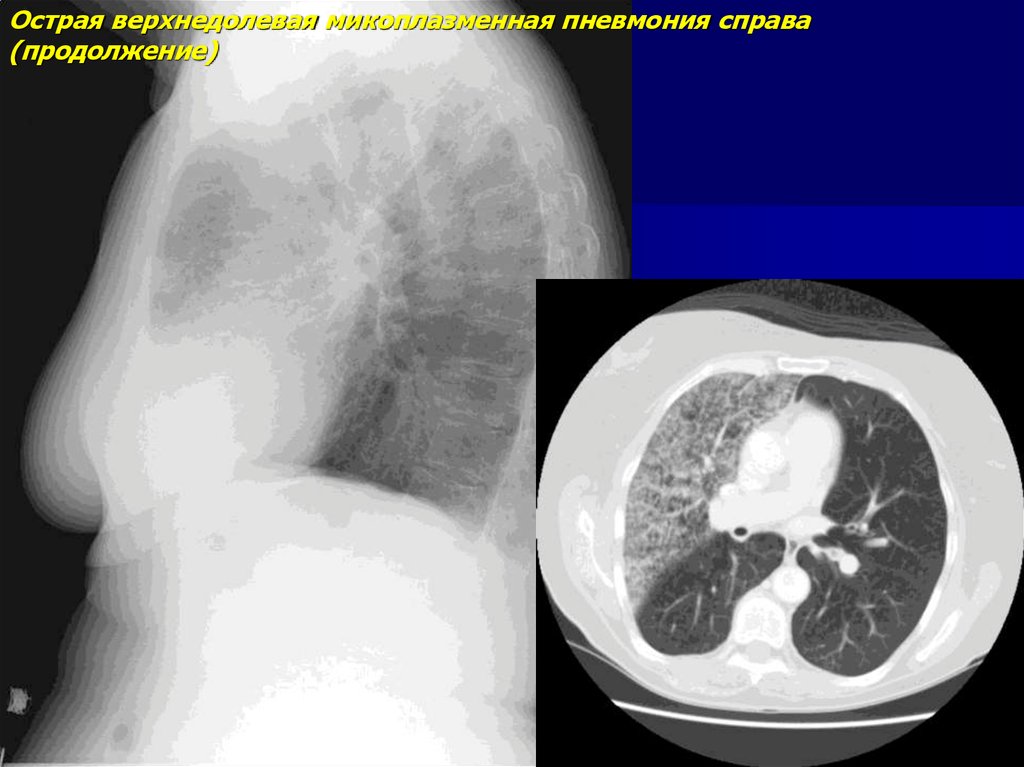

Острая верхнедолевая микоплазменная пневмония справа

(продолжение)